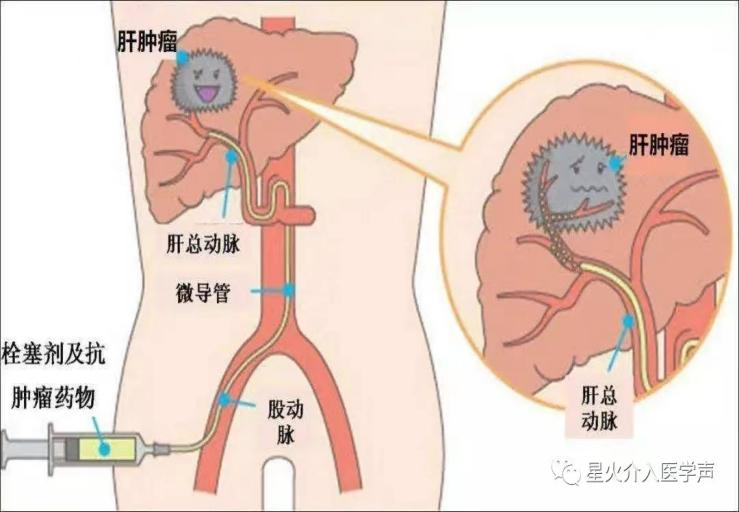

“还有一部分肝癌患者是由脂肪肝发展而来的。” 张华宇说,长久以来,人们都以为肝癌很难治愈,尤其是中晚期,一旦被确诊,感觉是被判了死刑,“实际上,现在对于肝癌的治疗发展很快,有很多手段,除了手术之后,对那些初诊不能手术的患者,还可以采用转化治疗,包括介入治疗,靶向免疫治疗等等,也就是先“保守”治疗,将肿瘤缩小,再寻求手术切除的机会。”